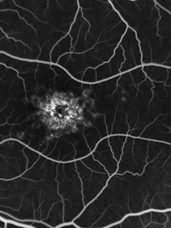

Résultats à 2 ans de l’étude SAGA : Gildeuretinol dans la DMLA Atrophique AAO 2024, DMLA22 octobre 2024

L’importance des suppléments AREDS dans la progression des lésions d’atrophie géographique AAO 2024, DMLA21 octobre 2024